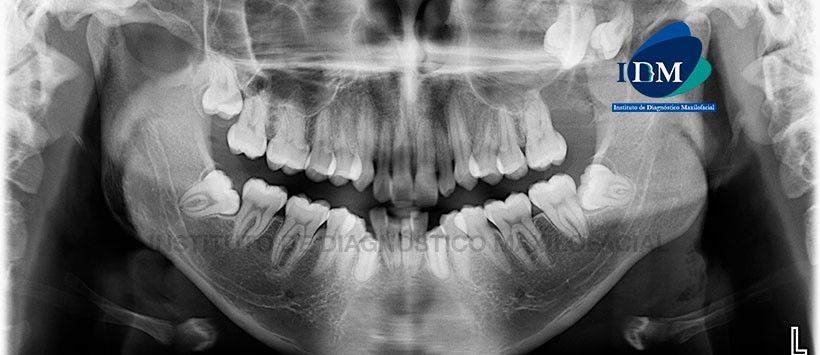

En la radiografía panorámica (Figura 1) se observa una imagen radiolúcida de límites definidos y bordes parcialmente corticalizados, localizado en la región posterior de la hemimaxila izquierda y que ocasiona la retención y desplazamiento cefálico de las piezas 2.7 y 2.8.

A la evaluación de la tomografía volumétrica (CBCT) cortes multiplanares (Figura 2, 3 y 4), transaxiales (Figura 5 y 6) y tangenciales (Figura 7), se aprecia la presencia de una lesión isodensa localizada en el maxilar superior izquierdo, que se extiende desde la cima del reborde alveolar hasta el piso de la órbita ipsilateral, de límites definidos y bordes parcialmente corticalizados. La lesión  ocasiona el ocupamiento del seno maxilar con obliteración del ostium; pérdida del reborde alveolar de zona de pieza 2.7 con aparente comunicación con la cavidad bucal; retención y desplazamiento cefálico de las piezas 2.7 y 2.8; erosión y leve expansión a nivel de la pared postero-lateral del seno maxilar y apófisis piramidal del lado izquierdo.